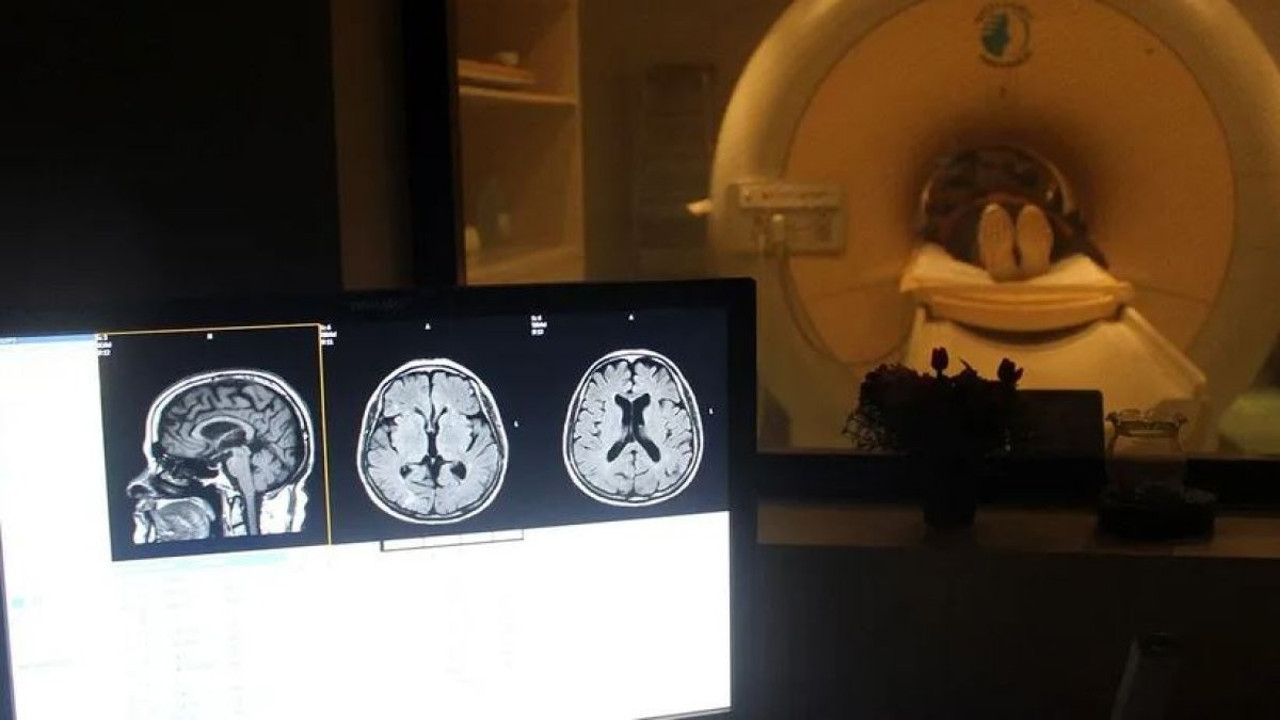

Beyninde 3 cm’lik iğne taşıyan kadın şaşırttı. Rusya’nın doğusundaki 80 yaşındaki kadının beynindeki iğne, doktorların yaptığı tomografi sonucu fark edildi. Kadının ebeveynlerinin, savaş zamanında çocuğunu düşürmek için iğne kullandığı ancak başarılı olamadığı tahmin ediliyor. İğnenin durumu kötüleştirebileceği endişesiyle alınmamasına karar verildi.